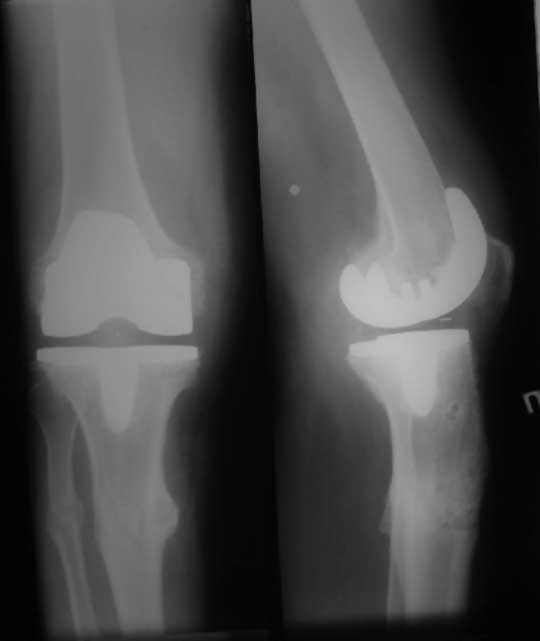

В настоящее время имеется разгибательная контрактура 10/5/0, на

операционном столе было 90/0/5, на момент выписки движения 50/0/0 в

надежде на дальнейшую разработку. До эндопротезирования 40/10/0.

Глубокая инфекция исключена. Ротация бедренного компонента в норме (по

КТ).

насколько для такого ограничения критична некорректная установка б/б компонента (я

намерял 7 град)?

Причина нынешнего состояния, артрофиброз?